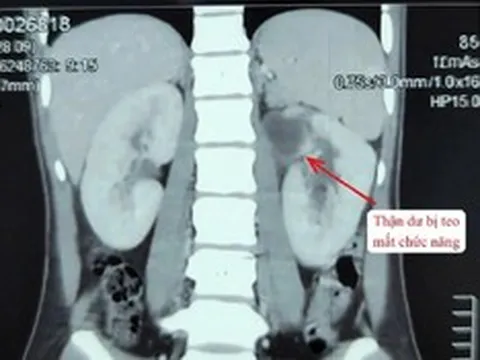

Khối u xơ tử cung gần 12 kg, to như bụng mang song thai trong người cô gái trẻ. Ảnh: BVCC.